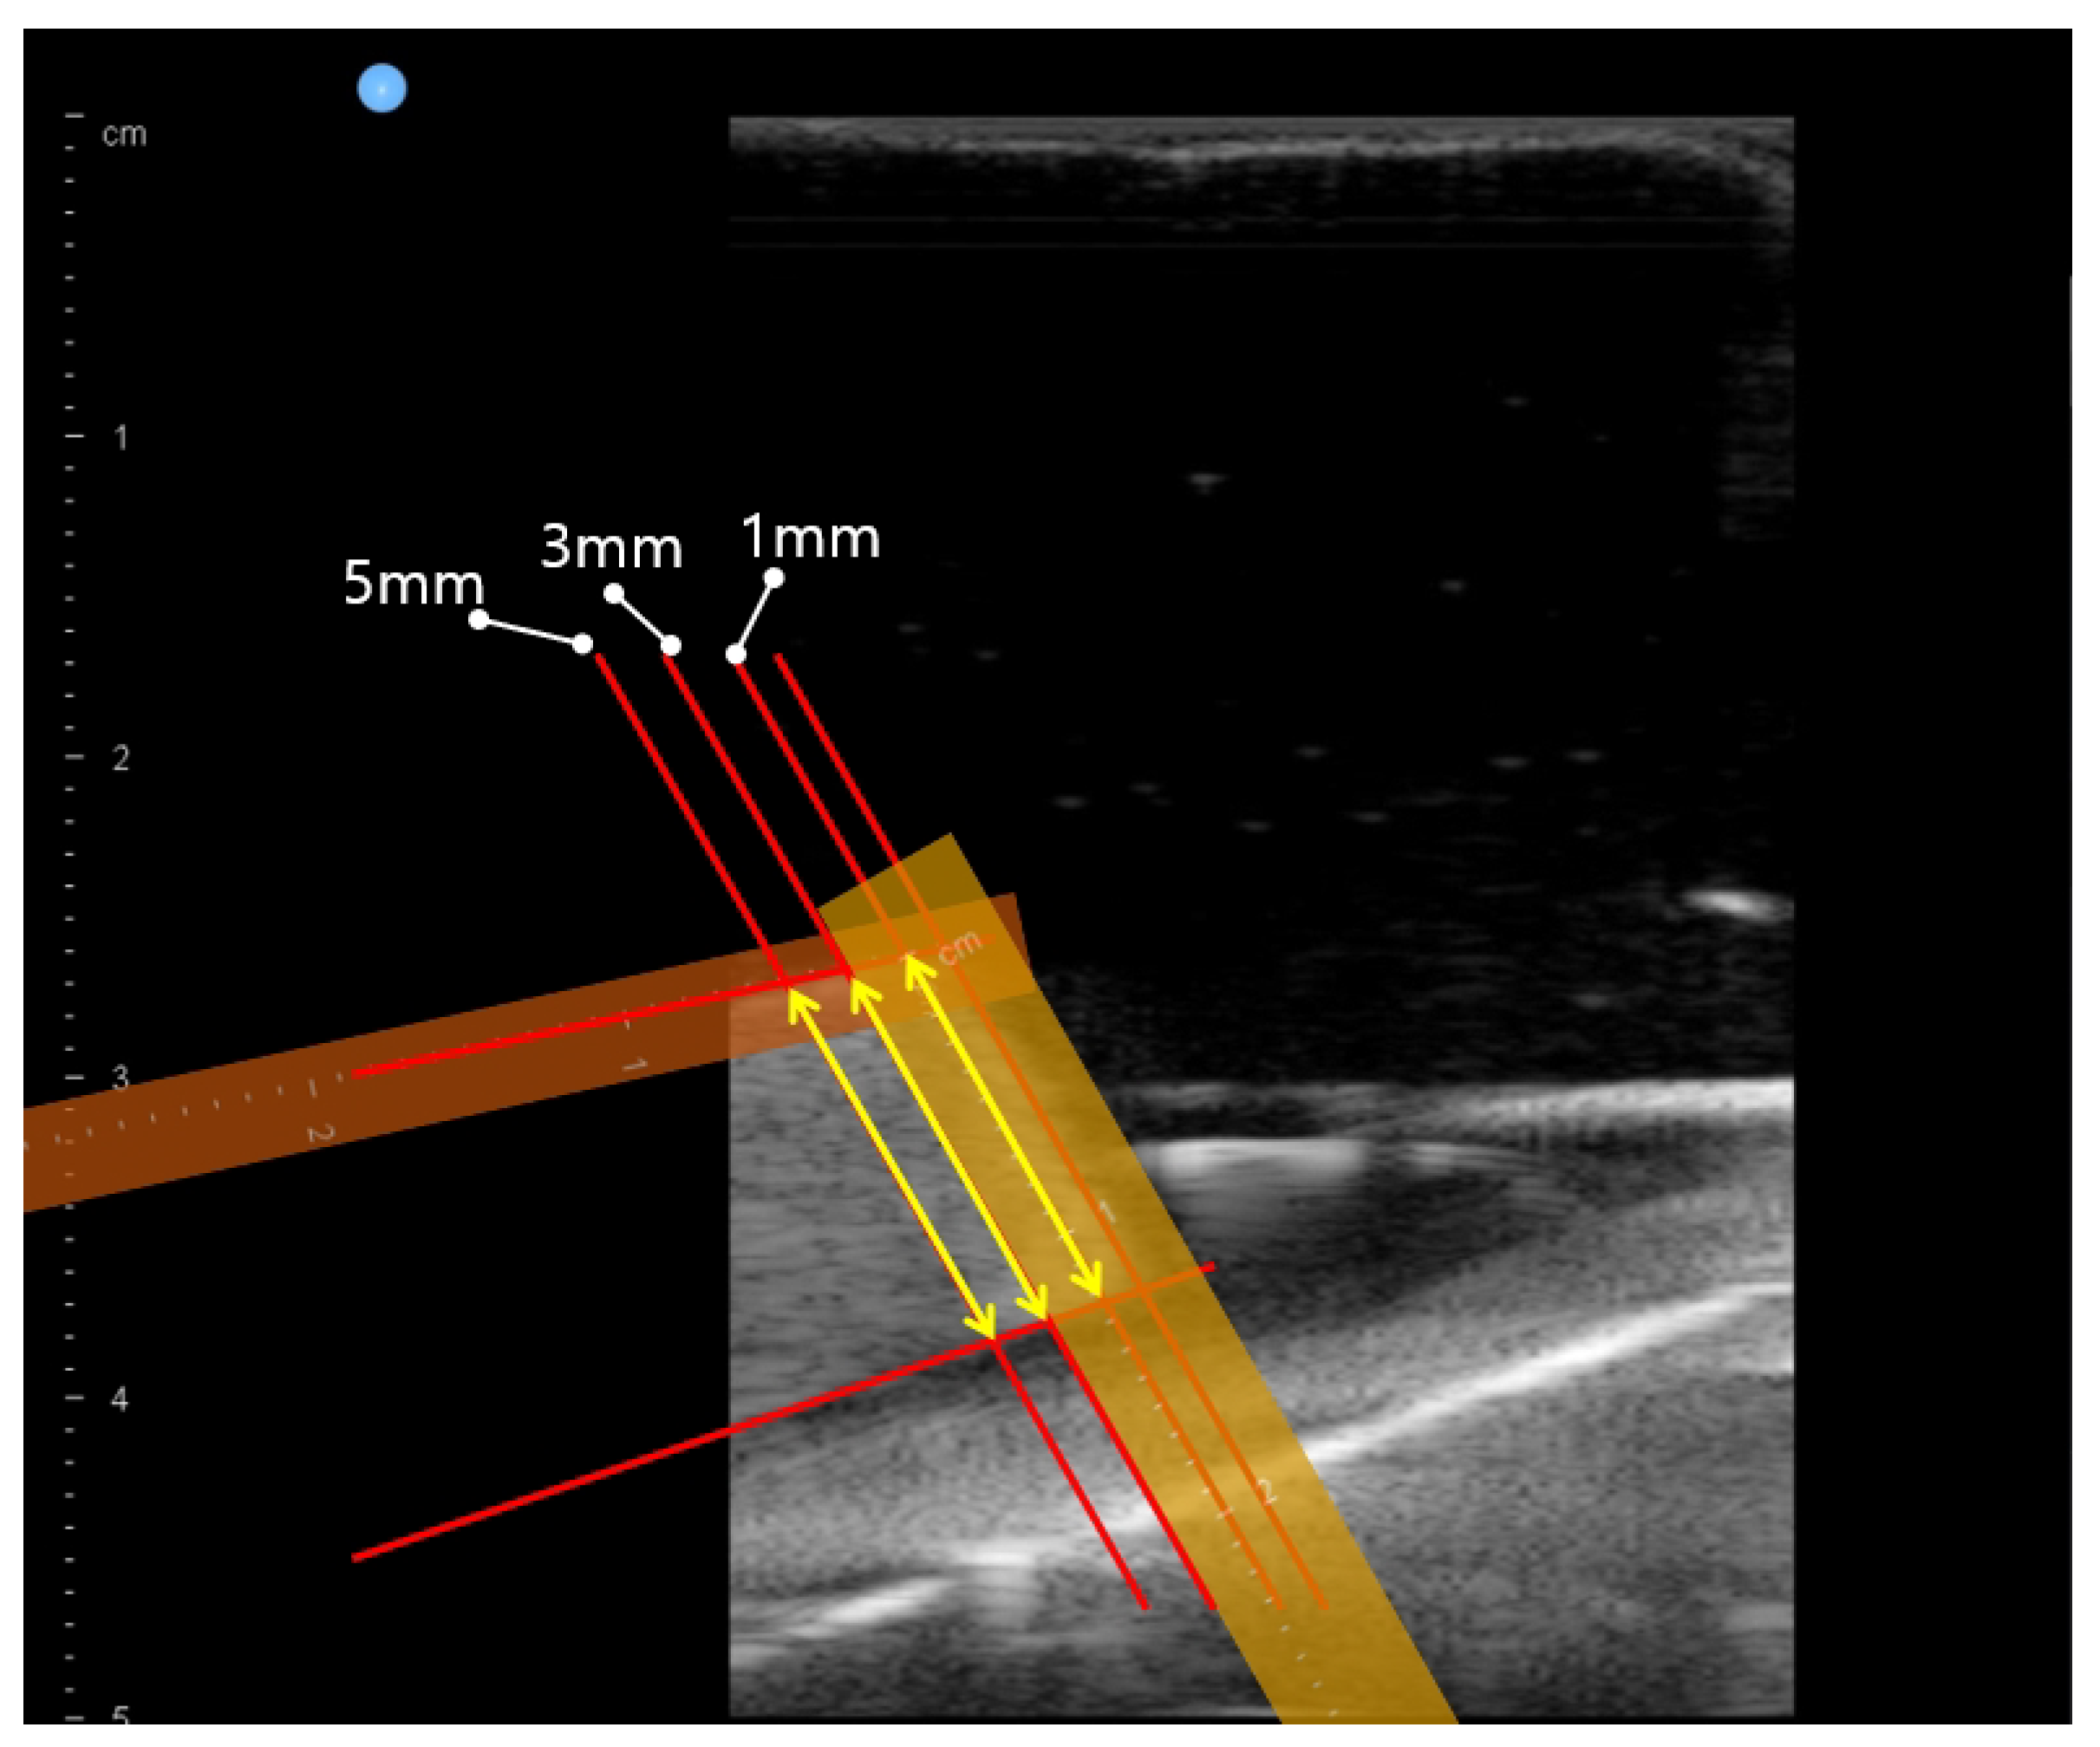

- An in-vitro test with bean curd-gelatin phantom was performed to validate the system and the proposed method. In opposition to the single-point muscle thickness measurements using ultrasound images in previous work [26], multiple-point bean curd thickness was measured.

3.2. In-Vitro Bean Curd-Gelatin Phantom Test Results

| Measuring Condition | Average of = −40∼30 | Std. Deviation of = −40∼30 | ||||

|---|---|---|---|---|---|---|

| 1 mm | 3 mm | 5 mm | 1 mm | 3 mm | 5 mm | |

| Operator #1 | 12.64 | 12.80 | 12.84 | 0.31 | 0.28 | 0.24 |

| Operator #2 | 12.54 | 12.74 | 12.74 | 0.33 | 0.30 | 0.30 |

| Operator #3 | 12.59 | 12.74 | 12.73 | 0.38 | 0.39 | 0.34 |

| Operator #4 | 12.56 | 12.73 | 12.74 | 0.39 | 0.38 | 0.36 |

| Operator #5 | 12.57 | 12.73 | 12.77 | 0.35 | 0.36 | 0.31 |

| Average | 12.58 | 12.75 | 12.77 | 0.35 | 0.34 | 0.31 |